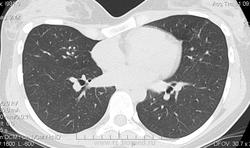

Коллеги, очень нужна ваша помощь. Обратились за консультацией ко мне, ну а я, разумеется, в свой любимый сайт, КТ-шник из меня плачевный. Девушка, 21 год, после прохождения очередной флюорографии отправлена на КТ. Жалоб не предъявляет, анамнез чистый, на предыдущих ФЛГ патологии не обнаружили (к сожалению архив и последний снимок не предоставили, только КТ-шки). Подскажите, пожалуйста, что за патология? Если нужно, скину ссылки на дикие файлы.

Мое мнение очаговый туберкулез S5 верхней доли левого легкого.

Необходимо дифференцировать с периферическим образованием.

Михаил, а контраст вводил? Выглядит как сосудистая мальформация. Попробуй МИП построение, возможно, увидишь связь с сосудами. Ну, и кривая грудная клетка.

Сосудистая мальформация более вероятна.

Для подтверждения сосудистой аномалии и снятия вопроса о туберкулезе достаточно сделать контрастное исследование.

КТ для меня - белая пустыня. Но, отдельные очаги бронхогенного распространения (отсева), на мой взгляд, имеют место быть.

На цифровике часть изменений не видна, а у девочки аккурат за передним отрезком 4-го ребра и прячется), размеры-то 1х1,25 см.

Посмотрел аксиалы, что тут выложены. Не сложилось впечатления о мальформации... На первое место очаговый тубер бы написал исходя их предоставленного материала.